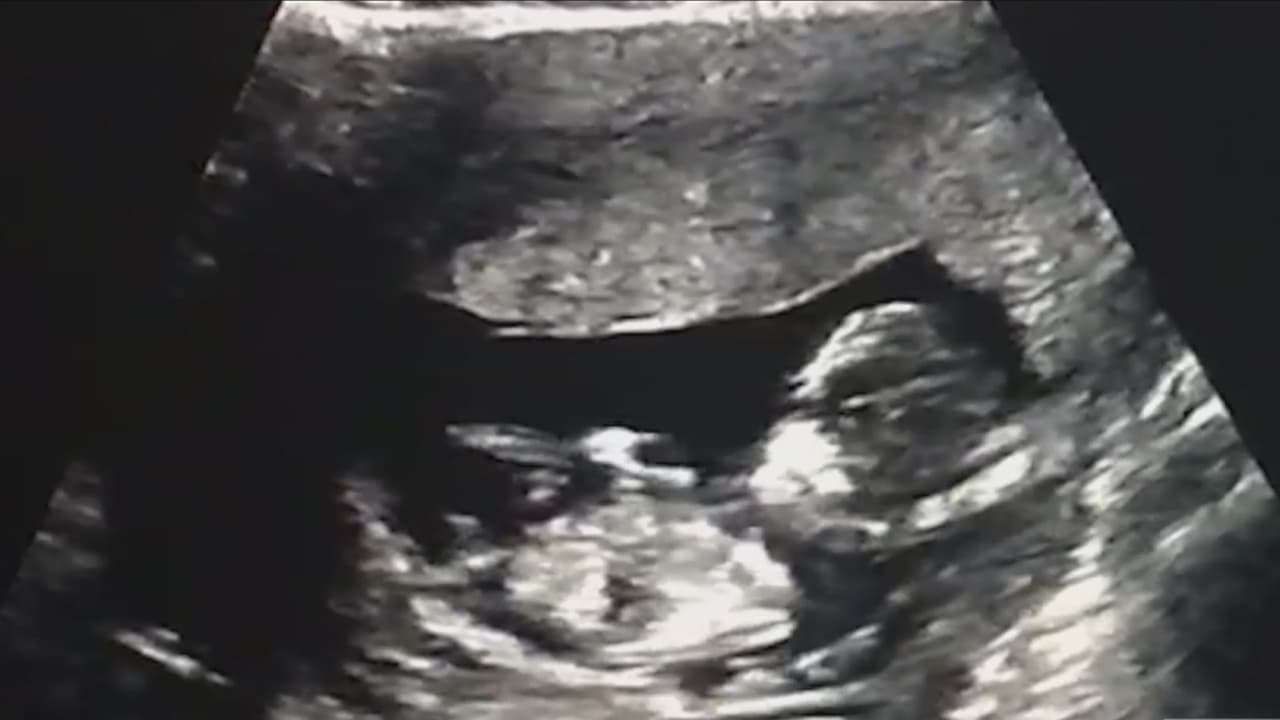

¿Qué tan riesgoso es que a una embarazada se le rompa la fuente antes de tiempo?

El 10% de los embarazos en Estados Unidos son prematuros. Para prevenir este tipo de incidentes se pide a las mujeres tener una dieta balanceada, no fumar, evitar infecciones y demás.